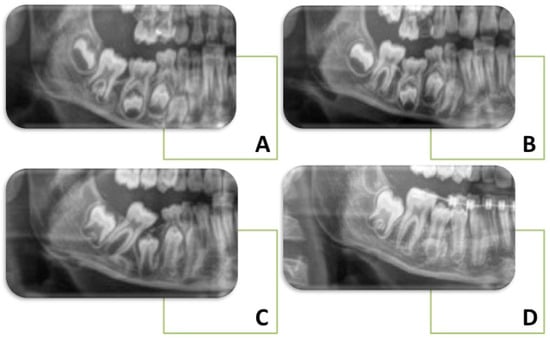

- Eşian, D.; Bica, C.I.; Stoica, O.E.; Dako, T.; Vlasa, A.; Bud, E.S.; Salcudean, D.; Beresescu, L. Prevalence and Manifestations of Dental Ankylosis in Primary Molars Using Panoramic X-Rays: A Cross-Sectional Study. Children 2022, 9, 1188. [Google Scholar] [CrossRef]